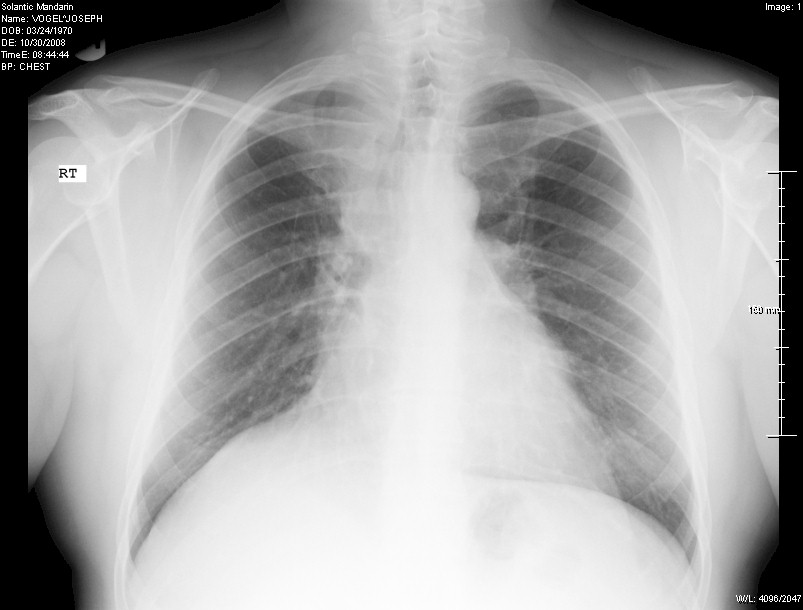

X-Ray of my chest done by Solantic and indicated as

"normal lung" in October 2008:

When you compare this to the example of a real normal one above, you can see how

the right side it shifted up and the upper right area is not as dark.

The dark area indicates "air" in the lung (when you get a chest x-ray they ask

you to breath in deep). Also note on the left hand side you see more of a

full lung, remembering that the heart is in front of the lung on that side so it

does not show up as dark.

But you can tell something is not quite right with the right lung presentation.

Nonetheless, the Solantic doctor indicated it as "normal

lung".